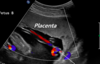

What pathology does this depict? [1]

Placenta praevia Fig 3 – Anterior placenta previa. The placenta (arrow) has covered the internal os completely (arrowhead).